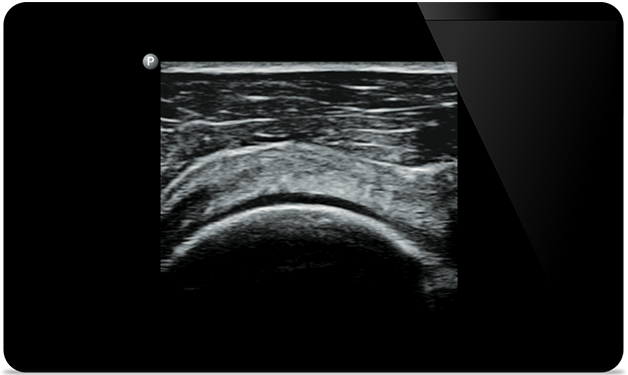

Lumify helps you see the fine details in muscles, joints, ligaments, tendons and cartilage to make a more accurate diagnosis of injuries.

Lumify can help you assess patients from head to toe, whether it’s plantar fasciitis, tendonitis or bursitis in the patellar tendon, or even shoulder instability in the rotator cuff.

Get the clarity of larger ultrasound systems with Lumify

SonoCT reinforces real tissue imaging while eliminating random artifacts. This technology produces images superior to conventional imaging in up to 94% of patients.